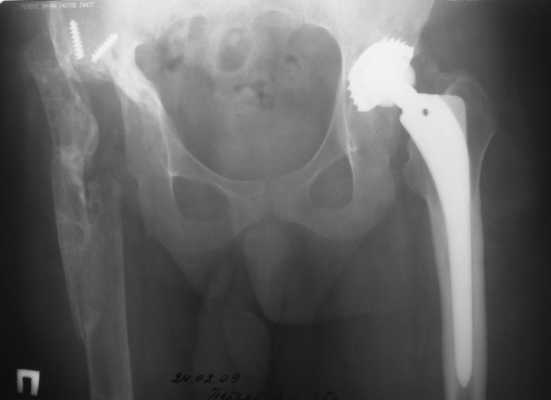

1999г. ревизионное протезирование правого ТБС и вновь инфекционная нестабильность - протез удален.2000 г. установлено кольцо Мюллера и ножка типа Споторно справа (рис. 1).

2003 г. нестабильность тазового компонента (рис. 2) - протез удален.